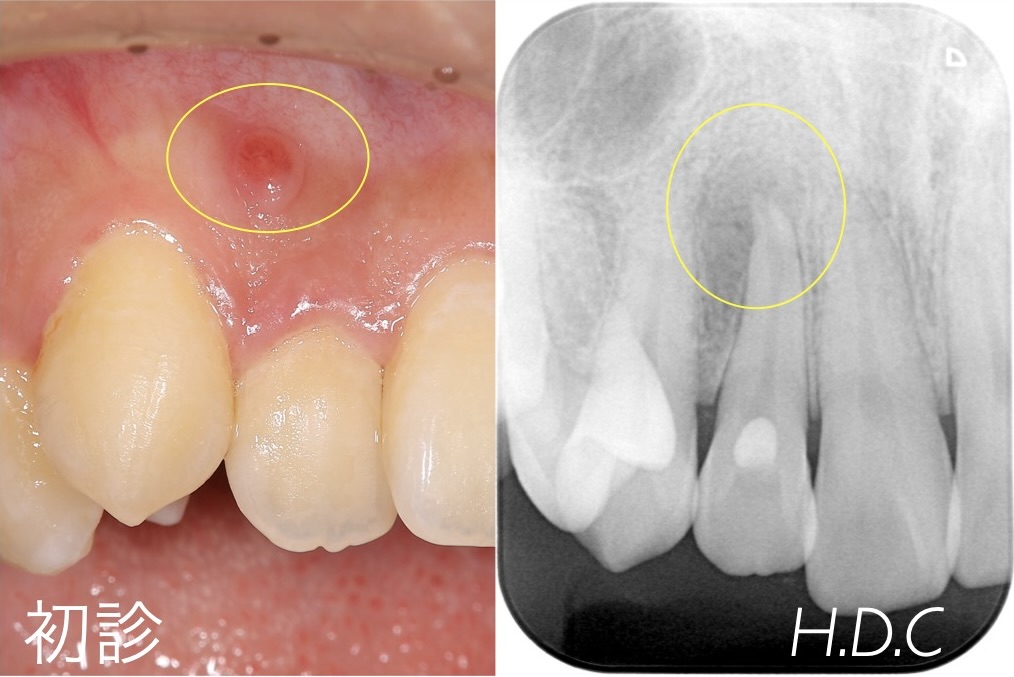

根管治療例③

- 年齢・性別

- 30代 男性

- 主訴

- 右上の前歯の歯肉が腫れた。

- 診断名

- 根尖性歯周炎

- 治療内容

- 根管治療後、コンポジットレジンにて修復治療を行いました。

- 治療期間

- 約3ヶ月

- 治療費用

- 保険診療

- リスク

- 根尖性歯周炎の再発、歯根破折、コンポジットレジンの破折など